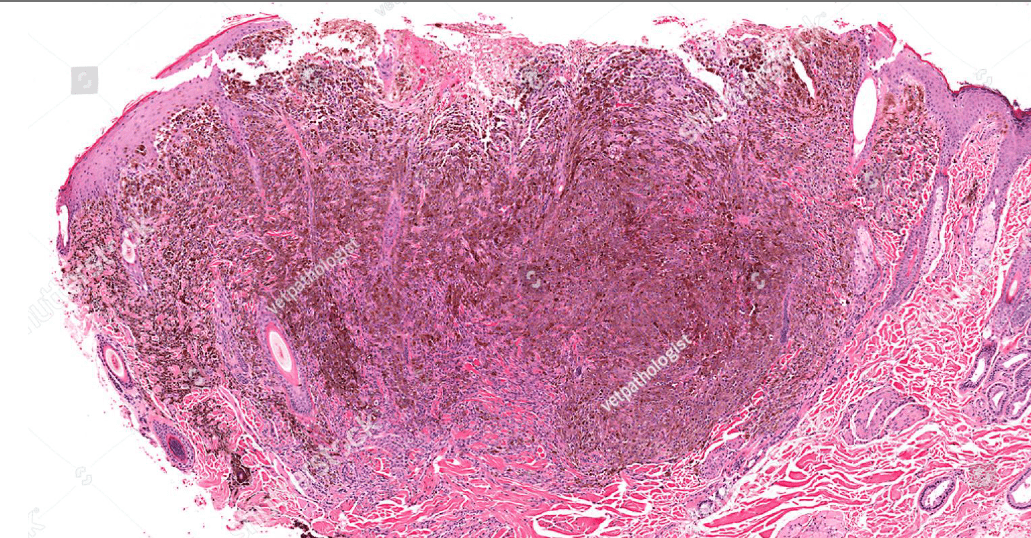

skin?

(melanin pigment)

(circumscribed/infiltrative)